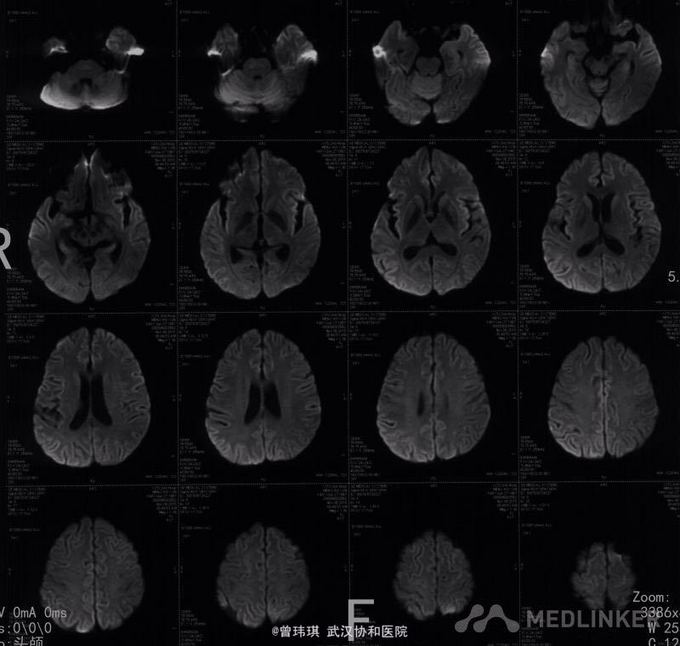

入院查体:四肢肌肉、胸骨、椎骨、膝关节压痛。双上肢肌力Ⅳ级、左下肢肌力Ⅱ级、右下肢肌力Ⅲ级;胸2平面以下痛觉减退,双侧肱二头肌、肱三头肌腱反射(++)、膝腱及跟腱反射(+-++)、左侧霍夫曼征阳性、双侧巴彬斯基征阳性。 骨髓穿刺(第一次):骨髓增生稍低,出现浆细胞卫星现象,并有瘤样改变,嗜血细胞增多,骨髓小粒中造血细胞增多。 复查骨髓穿刺(第二次):增生细胞稍低,浆细胞有瘤样改变,网状细胞、异常吞噬细胞明显。 再次复查骨髓(第三次):增生性骨髓,巨核细胞数正常,血小板减少,粒红可见轻度病态造血现象,浆细胞、网状细胞易见。 外院:血清Kappa轻链4.95g/L;免疫球蛋白G1870mg/L(723-1685),免疫球蛋白A 410mg/dl(69-382),免疫球蛋白M 31mg/dl(63-277),KAP 545mg/ml(170-370),LAM 273mg/dl。 肿瘤标志物:NSE 53.88ng/ml,铁蛋白 2476ng/ml。 自身抗体谱、血T-SPOT、G试验、GM试验、肝炎系列、梅毒、艾滋抗体等均未见异常。 PET提示右侧下鼻甲葡萄糖代谢增高,骨髓及脾脏大、葡萄糖代谢增高。 头颅MRI+颈椎+胸椎MRI扫描:1、右侧侧脑室、豆状核及外囊异常信号影,考虑脑梗塞,建议DWI检查;2、颈椎间盘突出(颈4-5、5-6,中央型);颈6椎体骨岛;3、胸3-6椎体水平椎管内异常信号影,建议增强扫描。